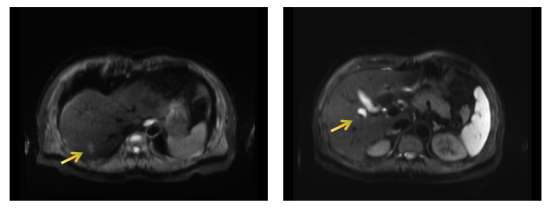

2020.09.25 上腹部MRI影像:肝内多发占位性病变(6个),考虑多发转移瘤。

image.png

图2 初诊时上腹部MRI